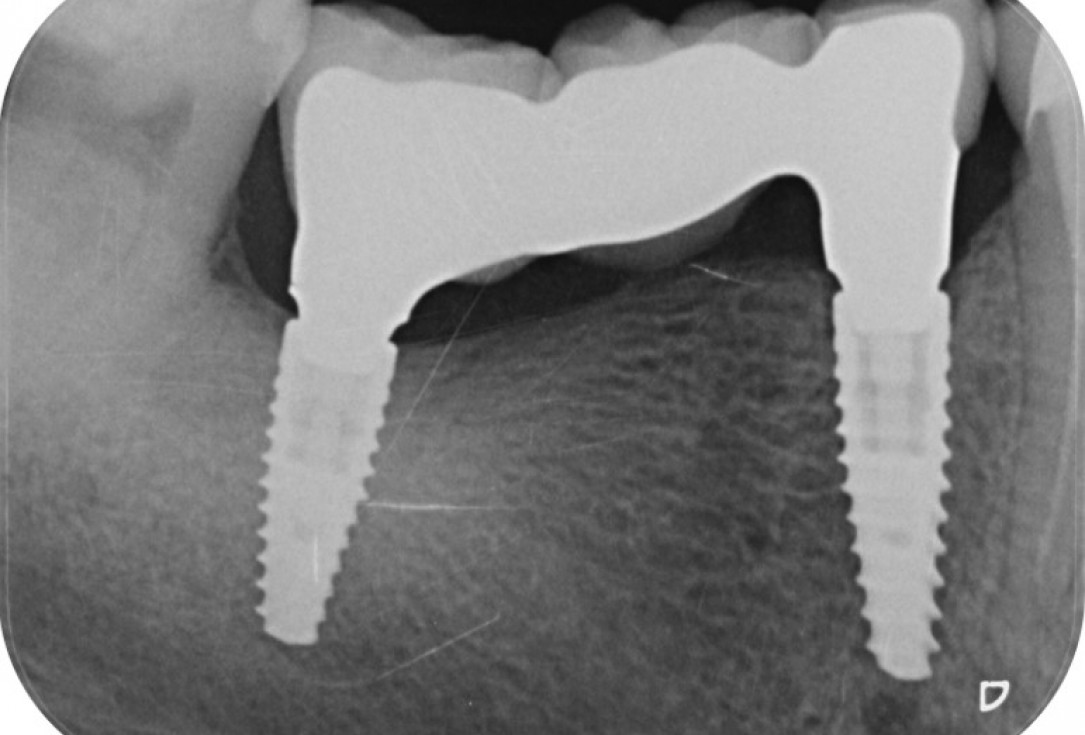

9/9 - X-ray control shows stable tissue for ponticPeri-implant soft tissue augmentation for pontic with mucoderm® - Dr. M. Frosecchi